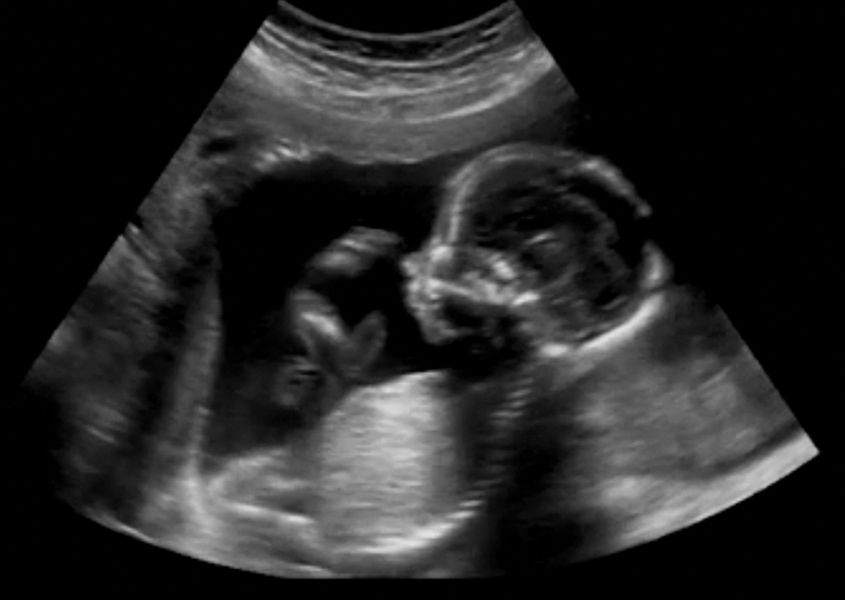

Als alles goed is, zie je tijdens de twintig wekenecho niet veel meer dan bij de echo’s daarvoor. Een tevreden spartelende brei van zwart-witte vlekken die, als je wat fantasie gebruikt, je kindje moet voorstellen. De echoscopist ziet echter veel meer en loopt je kindje stapsgewijs helemaal na. Zo wordt er gekeken of je kindje misschien een waterhoofd heeft, een schisis (zogenaamde ‘hazenlip’), een open ruggetje, klompvoetjes of (andere) afwijkingen aan de organen. Ook wordt gekeken naar de ligging van de placenta, of je kindje goed groeit en of er voldoende vruchtwater is. Aangeboren afwijkingen (van zeer ernstig tot prima mee te leven) komen bij zo’n 5% van de levend geboren kinderen voor. Houd dus, als je erg zenuwachtig bent, jezelf voor dat 95% van de kinderen gezond ter wereld zal komen.